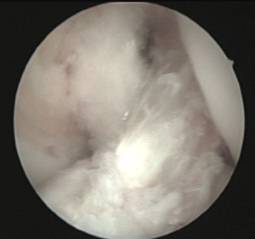

En aquells pacients immadurs amb inestabilitat anterior del genoll simptomàtica utilitzem la reconstrucció artroscòpica transepifisària amb tendó semitendinós del pacient.

S’evita el dany del cartílag de creixement mitjançant l’ús de tunelitzacions retrògrades (sistema de retroconstrucció) que ens permet restituir la funcionalitat de l’articulació sense afectar el cartílag de creixement i mantenint la isometria de l’empelt implantat.